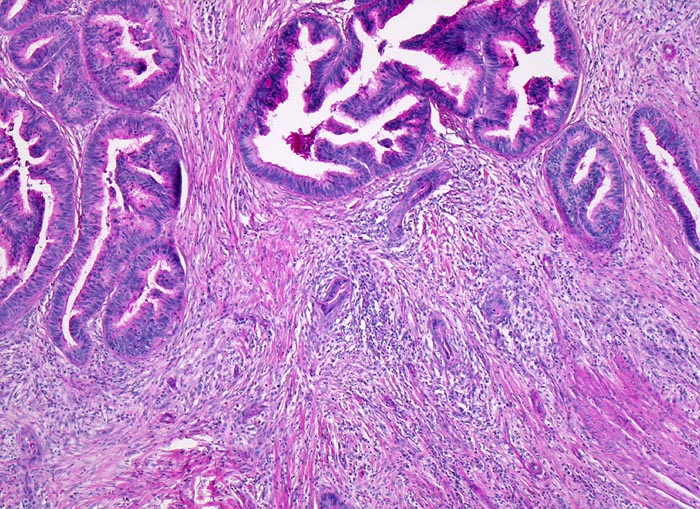

PathoPic – image database / PathoPic ID 4985 - mässig differenziertes Adenokarzinom

mässig differenziertes Adenokarzinom

Karzinomdrüsen mit komplexer Architektur in der Submukosa. Dichtes desmoplastisches Stroma und Entzündungszellen umgeben die Tumordrüsen.

Der Patient wird wegen neu aufgetretener Obstipation abgeklärt. Koloskopisch kommt im Kolon sigmoideum ein polypoider, das Lumen stenosierender stark karzinomverdächtiger Herd zur Darstellung. Die Biopsie zeigt atypische Drüsen mit desmoplastischer Stromareaktion stark verdächtig auf ein invasives Karzinom. Da an der oberflächlichen Biopsie ein invasives Wachstum nicht nachgewiesen werden kann, lässt sich das Karzinom jedoch nicht beweisen. Es wird eine Sigmaresektion durchgeführt.